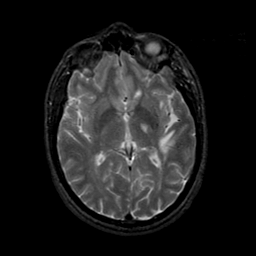

MR Study #21, November 3, 1991 -- Slice #25